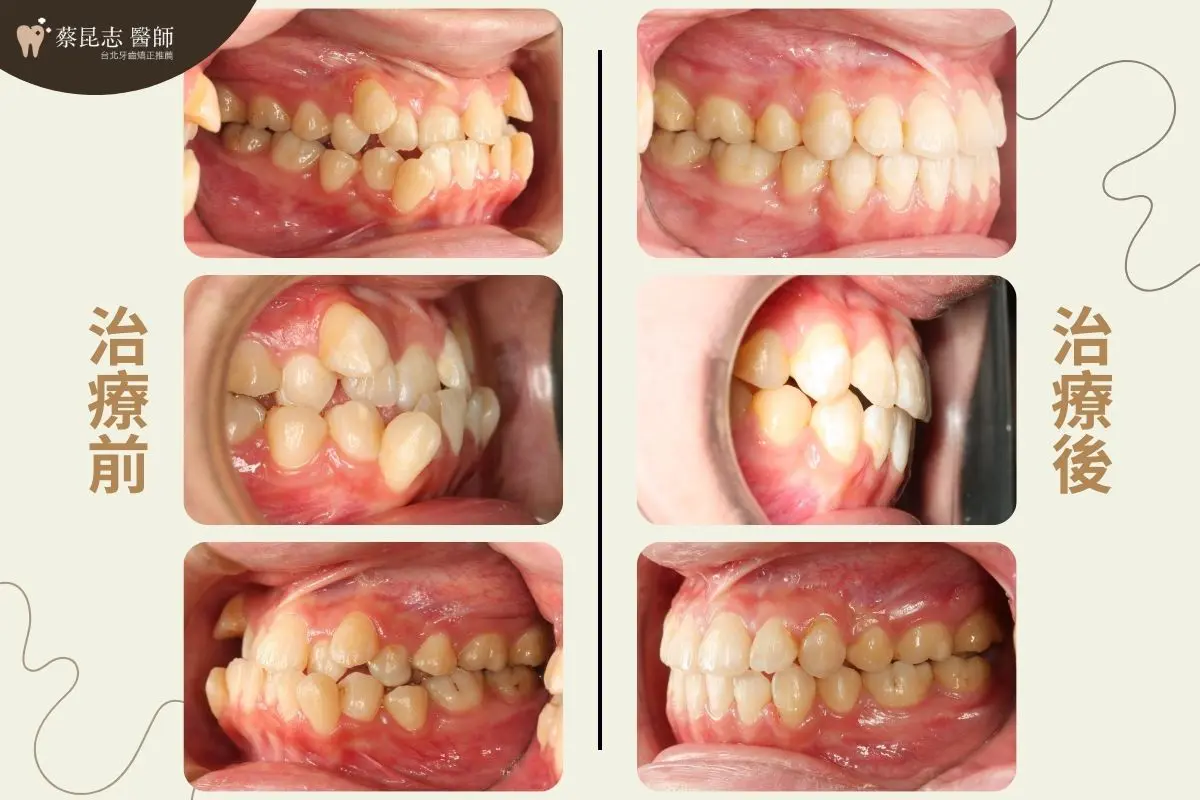

治療前可以見到因為上下顎前牙嚴重擁擠、上顎高位犬齒,所造成的不美觀笑容。

又因為下顎前牙過於外暴、上下顎前牙咬合與正常咬合相反的錯咬,所造成的側面輪廓下唇的部分過於外凸。

治療計畫是拔除上、下顎左右兩側各一顆第一小臼齒,讓嚴重擁擠上下顎前牙,有空間可以排整齊

將上、下顎前牙後縮,恢復上下顎前牙正常咬合,並改善側臉輪廓下唇過於外凸之外觀,讓側臉下巴輪廓線條更加協調。

前牙錯咬戽斗案例-結果分享

前牙錯咬戽斗矯正前後臉型變化 前牙錯咬戽斗矯正前後口腔變化 前牙錯咬戽斗矯正前後口腔側面變化 前牙錯咬戽斗矯正前後門牙變化 前牙錯咬戽斗矯正前後嘴型變化 前牙錯咬戽斗矯正前後正面x光變化 前牙錯咬戽斗矯正前後側面x光變化